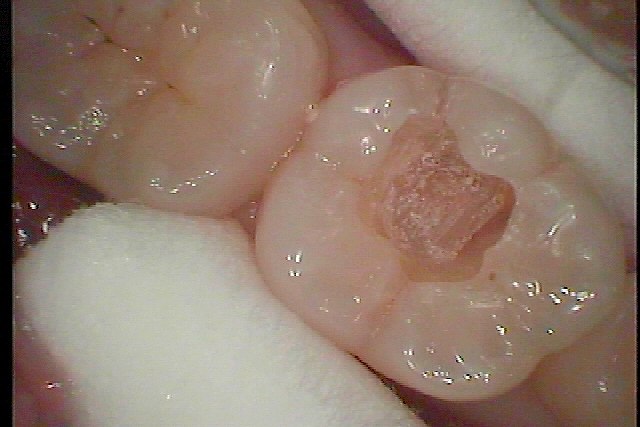

虫歯の治療です。 外見以上に虫歯が進行していることがあります。| |広島市安佐南区の歯科医院 虫歯の治療です。 外見以上に虫歯が進行していることがあります。 トップ お知らせ・ブログ 虫歯の治療です。 外見以上に虫歯が進行していることがあります。 虫歯の治療です。 外見以上に虫歯が進行していることがあります。 Web診療予約 初めての方へ 選ばれ続ける理由 院内設備について 歯が痛いしみる一般歯科 歯がぐらぐらする歯周病 健康な歯を保ちたい予防歯科 子供の虫歯予防をしたい小児歯科 銀歯をセラミックに審美歯科 白い歯を目指しませんか?ホワイトニング 矯正専門医がいるので安心矯正歯科 抜けた歯を補いたいインプラント・入れ歯 医院案内 スタッフ紹介 メリィハウス歯科クリニックオフィシャルホームページ ラベンダー歯科クリニックオフィシャルホームページ お知らせ・ブログ ホーム 診療科目 一般歯科 歯周病治療 予防治療 小児歯科 審美治療 ホワイトニング 矯正歯科 入れ歯・インプラント マウスピース矯正 初めての方へ 院長・スタッフ 設備紹介 医院案内・アクセス メニューを閉じる